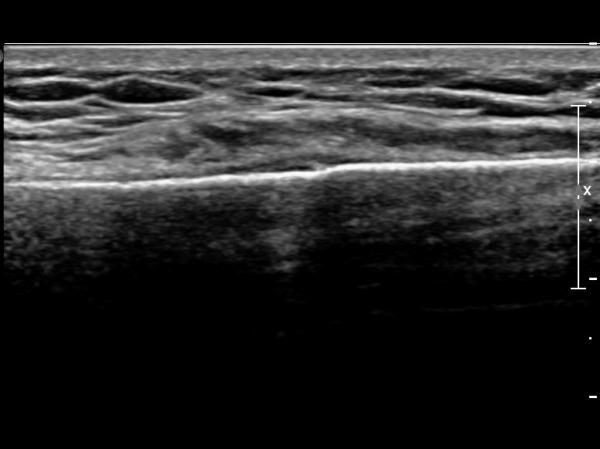

ŽÃËÀÚ¸¦ ¾à°£ ¸»´ÜÀ¸·Î À̵¿ÇÏ´Ï ¿¬ºÎÁ¶Á÷ ºÎÁ¾ÀÌ ´õ¿í ½ÉÇÏ°Ô °üÂûµÇ°í(»çÁø 2),